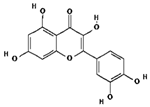

| Compound Name | Pubchem ID | Molecular Formula | Molecular Weight (g/mol) | Drug Likeliness | Bioavailability Score | BBB Permeant | Structure |

|---|---|---|---|---|---|---|---|

| Stigmasterol | 5280794 | C29H48O | 412.7 | 0.62 | 0.55 | No |  |

| Quercetin | 5280343 | C15H10O7 | 302.23 | 0.52 | 0.55 | No |  |

| Kaempferol | 5280863 | C15H10O6 | 286.24 | 0.50 | 0.55 | No |  |

| beta-Sitosterol- beta-D-glucoside | 12309055 | C35H60O6 | 576.8 | 0.5 | 0.55 | No |  |

| beta-Sitosterol | 222284 | C29H50O | 414.7 | 0.78 | 0.55 | No |  |

| Racemosol | 624971 | C21H24O4 | 340.4 | 0.36 | 0.55 | Yes |  |